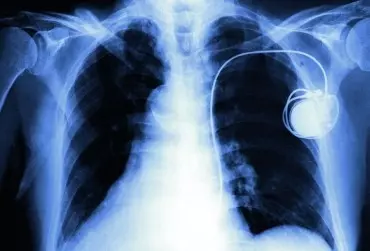

Rehabilitacja chorych po wszczepieniu urządzeń do stymulacji serca – zalecenia ogólne

Wszczepienie urządzenia do stymulacji serca zmienia jakość życia chorych. Ważną i nieodzowną składową procesu leczenia jest sfera somatyczna, zgodnie z zasadą „Wszystko, co ma wpływ na pacjenta, wymaga uwzględnienia”. Wstępnie przeprowadzone badania w Poradni Stymulatorów Serca Wojewódzkiego Centrum Medycznego w Opolu pokazują, że jakość życia pacjentów po wszczepieniu stymulatora serca znacznie się poprawia i jej poziom w ocenie pacjentów jest zadowalający. Jednocześnie ocena jakości życia jest niższa w porównaniu z osobami zdrowymi. W procesie leczenia i rehabilitacji chorych ze stymulatorami serca do oceny tej użyto kwestionariusz WHOQOL-BREF (The World Health Organization Quality of Life).